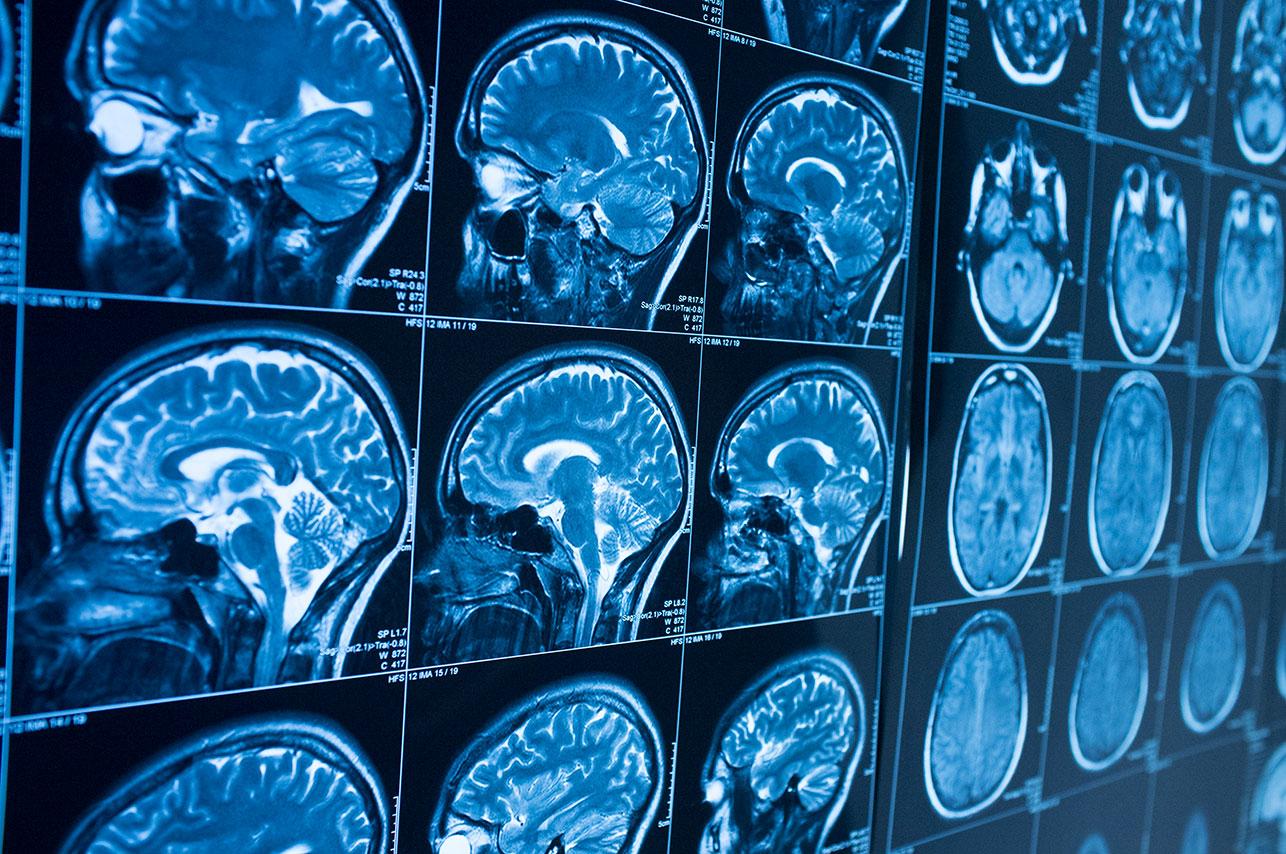

Current diagnostic procedures involve on-field testing of visual, verbal, and motor functions, followed by a brain scan that often is not sensitive enough to pick up the effects of a mild injury. The new blood test measures the levels of two brain proteins called UCH-L1 and GFAP; UCH-L1 is involved in disposing of damaged proteins, while GFAP helps to repair injured cells. Both are released into the bloodstream after a head injury.

The new test will help doctors more accurately predict which patients need brain scans. It only takes a few hours to get the results, and confirming high levels of UCH-L1 and GFAP will reduce the risks of radiation exposure—as well as the healthcare costs—of performing scans that are unlikely to be informative.